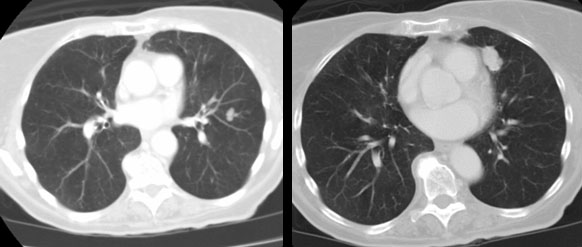

Example of the normal hilar interstitium: The images below are from a patient without bronchogenic carcinoma. The images demonstrate normal hilar lymphatic tissue (yellow arrow right image) which appears as a low density region between the bronchus and pulmonary vessel. A small calcified node is seen on the right (red arrow) in this patient with prior granulomatous disease. NOTE: Click image to enlarge.